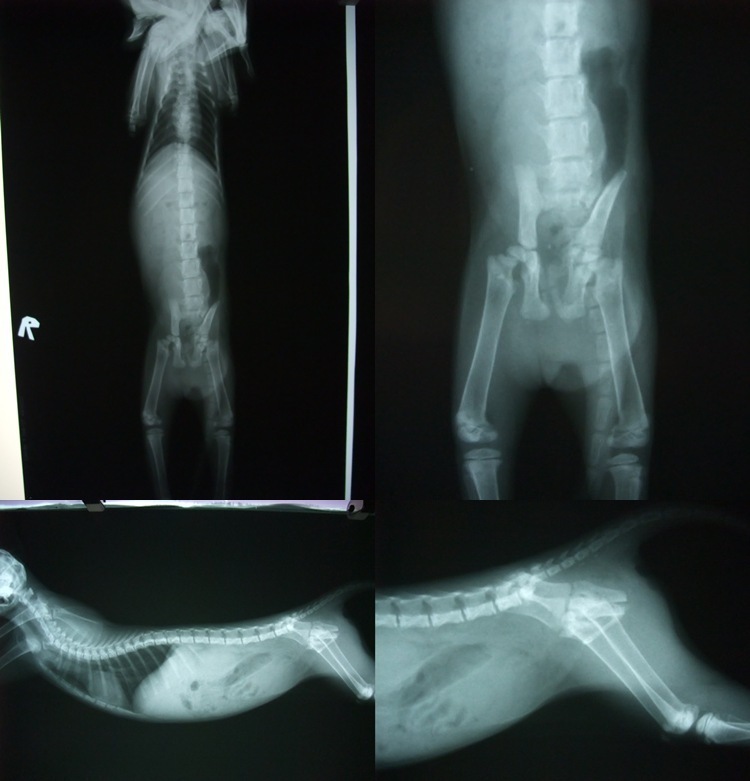

- 編號: 454

主題: 後肢遭重擊的小小貓 申請者姓名: Vivi Sung 花色: 申請日期: 2012-06-22 10:42:00 申請者部落格: 申請者臉書網址: 所在縣市/合作醫院: 台南市/奇異果動物醫院 治療費用: 4350元 需求人數: 6人 已結案 (2012-12-08 19:06:45) 報名人員: Athena Liu(已付款)、Nonie Huang(已付款)、Nancy(已付款)、Norman Wu(已付款)、Keyak(已付款)、Betty(已付款)、 候補人員: 白娃娃、小舟、 動物病情說明: 一隻項協會求援的小小貓咪,送院後腎上數飆高,後肢因為重擊骨頭也斷裂..可憐的小小貓咪,因為無法自行排尿.緊急手術中,尿道斷裂的地方也已經開始自行癒合上.這樣的手術對小貓咪來說,是艱苦的..即便先暫時處理,日後的造口,也必定會時常有感染的可能...

X光$400